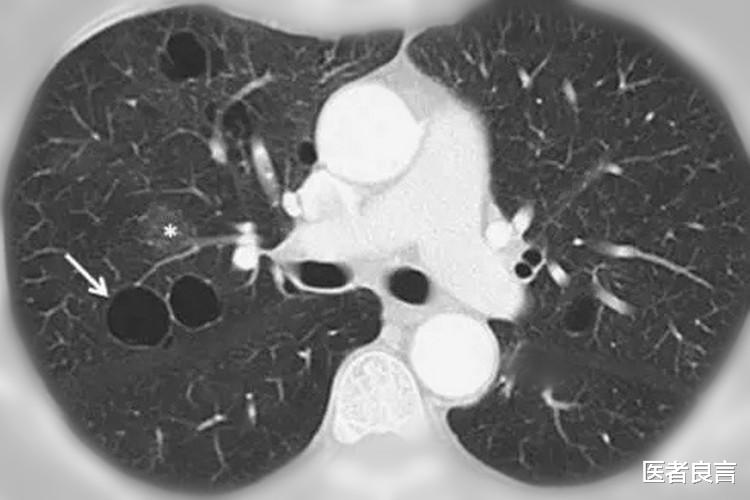

破裂的肺泡会相互融合 , 这样的话就会形成比原来肺泡更大的囊腔 , 也就是我们说的肺大疱 。 不过需要注意 , 肺大疱的直径一般来说是大于1cm的 , 而且里面还含有一些气体 。

说白了 , 肺大疱就是一种含有气体的空腔 , 较小的单个肺大疱一般来说都没有明显的症状 。 体积较大或者多个肺大疱就有可能会出现胸闷、气短等的症状 。